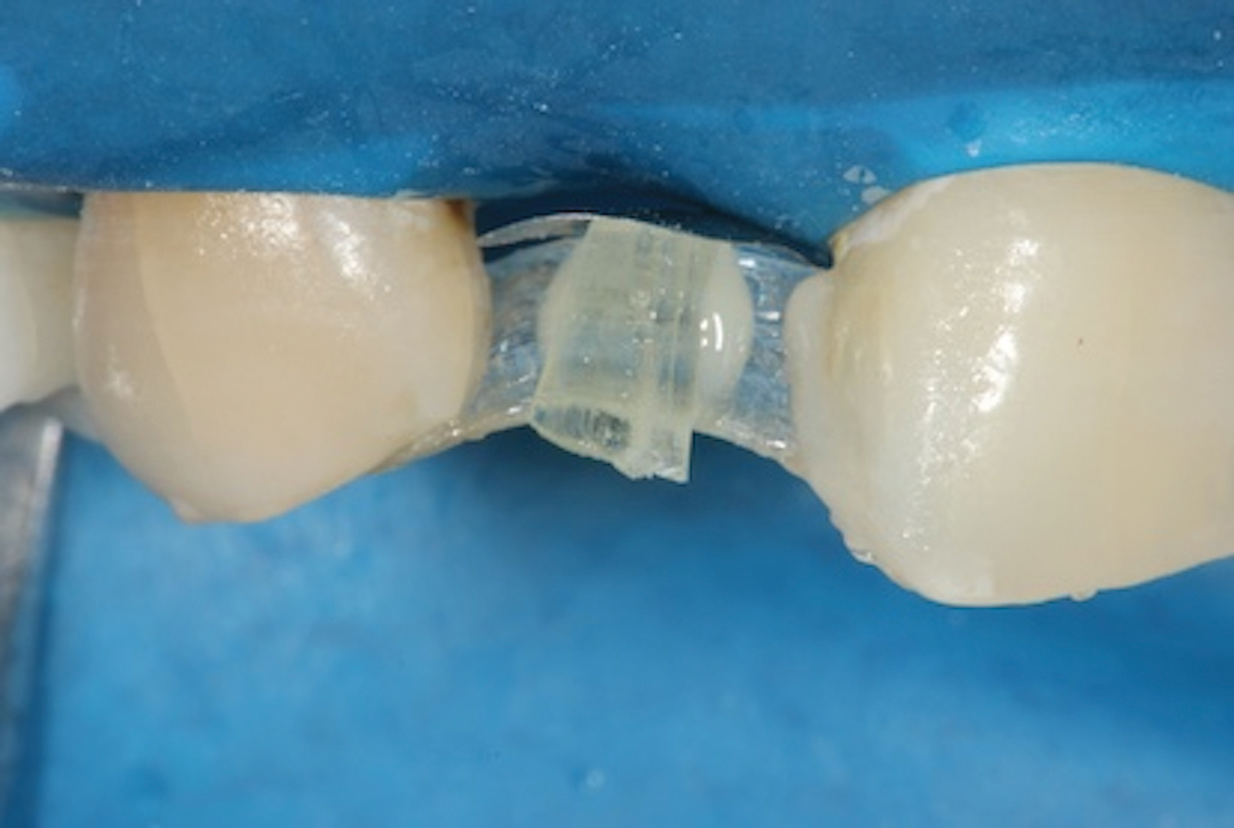

(9.) A sectional matrix band is positioned under the vertical fiber reinforcement such that its convex surface is touching the rubber dam in order to shape and position the tissue surface of the pontic as it is developed.

Figure 9

The most important part of the pontic regarding position, shape, and polish is the surface that will be in contact with the gingiva. An effective way of developing this contour is to employ a sectional matrix band. First, position the matrix band under the vertical fiber reinforcement such that its convex surface is touching the rubber dam (Figure 9). Next, cover the entire fiber assembly with an opaque shade of flowable composite. Direct the composite to flow under the fiber and along the matrix band to develop the desired emergence profile of the pontic. The contact with the band will create a smooth surface that will protect the soft tissue at the site without requiring any further handling (Figure 10 and Figure 11).